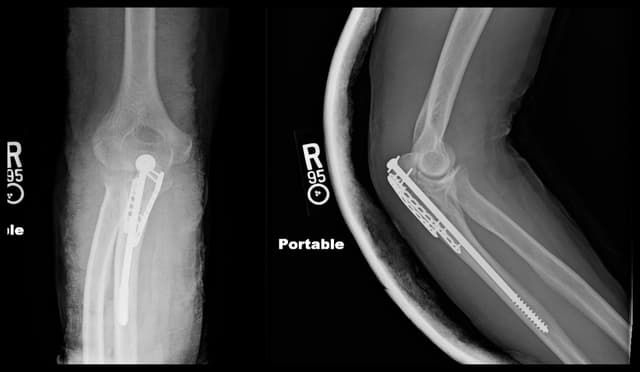

Imaging

Post-op